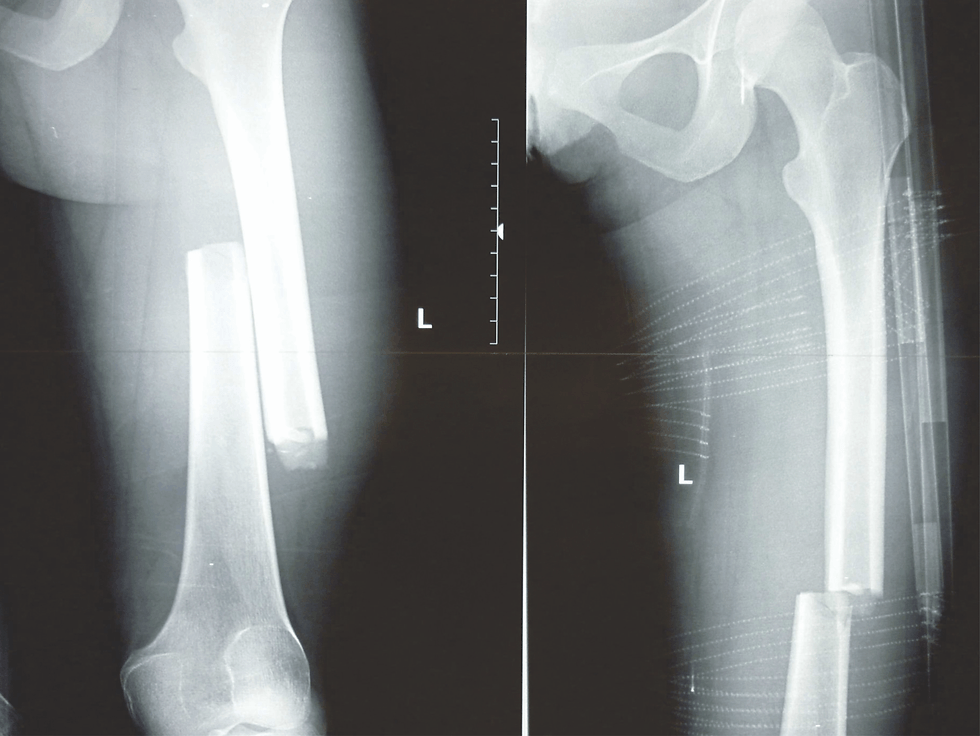

The CT-6 is a Leg Traction Splint designed for Pre Hospital Care and Patient transport, specifically in combat scenarios. It is primarily used on patients with mid-line femur fractures. The CT-6 helps relieve patient pain and prevents further damage to surrounding muscle and tissue while reducing the risk of death caused from severed arteries. The CT-6 is made of carbon tubing which snaps together via an internal bungee. A buckle secures the Ischial strap to the upper leg and groin. These buckles prevent accidental releases and are commonly used by US military forces. Traction is achieved with a 4 to1 purchase system using a small line to apply tension. This method results in a very precise and delicate form or traction that is also powerful enough to be effective on extra large adults. The CT-6 is extremely compact, light and strong. Not for sale here sorry, please contact us.

- Carbon Fiber Tubing: Corrosion resistant, temperature stabile, extremely high strength to weight ratio, x-ray translucent.